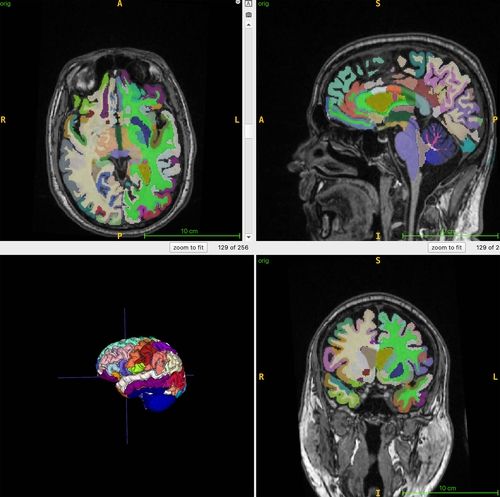

미국 워싱턴대 의대 연구진이 전신 MRI와 인공지능(AI) 분석을 통해 근육량과 복부지방이 뇌 노화 속도와 연관된다는 결과를 발표했다.

연구팀은 건강한 성인 1천164명(평균 55.17세)을 대상으로 총근육량, 내장지방, 피하지방을 정량화하고 MRI 기반 ‘뇌 나이’를 산출했다. 분석 결과 근육량이 많을수록 실제 나이와 뇌 나이가 모두 더 낮게 나타났다. 총근육량의 상관계수(rp)는 실제 나이 -0.2579, 뇌 나이 -0.2497로 통계적으로 유의한 반비례 관계였다.

또 내장지방 대비 근육 비율이 낮을수록 실제 나이와 뇌 나이가 더 높아지는 중등도 연관성이 확인됐다(rp 0.3755·0.3797). 반면 피하지방은 뇌 노화와 관련이 없는 것으로 나타났다.

연구팀은 “근육이 많고 숨겨진 복부지방이 적은 사람이 더 젊은 뇌를 가진다”며 “근육량 증가와 내장지방 감소가 알츠하이머병 등 뇌 질환 위험을 낮추는 데 도움이 될 수 있다”고 설명했다. 이번 연구 결과는 11월 30일부터 열리는 북미영상의학회(RSNA 2025)에서 발표된다.